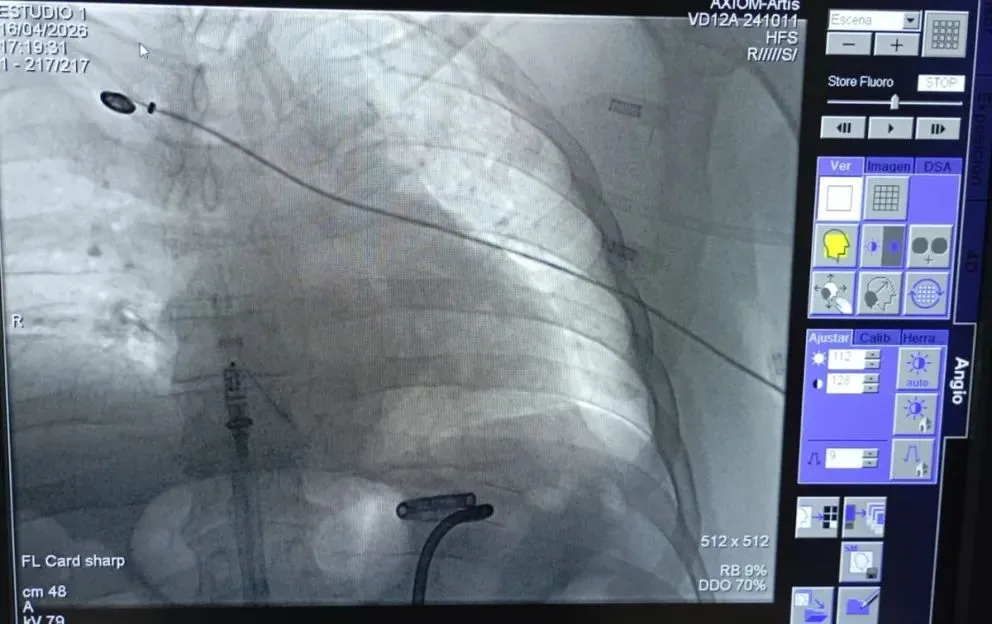

Durante una intervención de 40 minutos, un paciente recibió un marcapasos de altísima tecnología que le permitirá hacer vida común. Fue realizada por el equipo del Servicio de Electrofisiología de la Unidad de Cardiología de la Clínica Viedma.

El procedimiento estuvo encabezado por Martín Calvelo, jefe de Cardiología, y contó con la supervisión de Ariel Estévez, médico proctor especializado la implementación de estas cirugías, perteneciente a la empresa Medtronic (líder mundial en tecnología médica). Esta es la proveedora del dispositivo, denominado Micra AV2, que es 10 veces más pequeño que uno convencional, dura un 40% más y evita complicaciones al paciente.

“Para su colocación, es necesaria una intervención quirúrgica que consiste en implantar un generador de impulsos eléctricos (pila o batería) y un cable-electrodo endovenoso. Un extremo del electrodo se coloca en la cavidad interna del corazón y el otro extremo se conecta al generador”, explicó Calvelo.